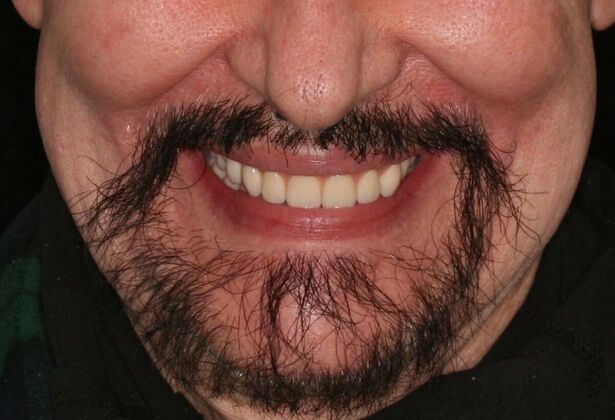

Patient had severe cavities throughout the mouth due to extreme dry mouth and history of use of tobacco. Patient was very discouraged as he had hated the idea of wearing dentures. Patient found Dr Bidra online and sought treatment and had all his teeth extracted and implants placed and new teeth installed all in 1 day! Patient was extremely satisfied with his transformation and eradication of all disease and bacterial infections.

Procedures : extractions, implants, All on 4 , Teeth in a day, no bone grafting and full mouth reconstruction with monolithic zirconia bridges.

Testimonial : "Dr.Bidra I cannot be thankful enough for the amazing treatment you have provided me so meticulously! I never thought this was possible but you made it happen. Thank you so much!